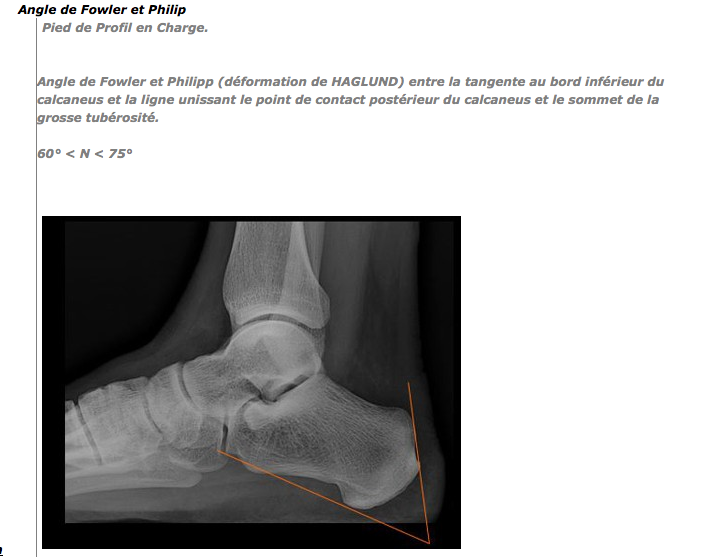

Si vous vous reconnaissez, relisez l’article et commencez par faire une radio à la recherche de cette anomalie anatomique typique (+ angle de Fowler et Philipp). Si la radio confirme le soupçon, il faut trouver un chirurgien spécialisé dans cette pathologie, opérer et patienter quelques mois sans rééducation.

Il se pourrait qu’il s’agisse de Haglund. Pour le confirmer, je vous propose de relire mon article et, si l’hypothèse semble « tenir la route », il faut faire une radio en insistant sur l’angle de Fowler et Philipp.

Il faut en effet qu’il y ait qu’il y ait un faisceau de présomptions : pseudo-tendinite, déformation du talon, angle de Fowler et Philipp… Ensuite, le médecin et l’orthopédiste doivent se prononcer.

Avant d’opérer, il faut un diagnostic très précis. S’il s’agit d’une maladie de Haglund, il faut ce que vous décrivez + un angle de Fowler et Philipp pathologique à la radio : voir l’article.

Monsieur,

Il faudrait donc savoir s’il y a Haglund ou pas. Essentiel = cet angle : https://orthopedie.files.wordpress.com/2007/03/capture-d_ecc81cran-2013-02-23-acc80-19-09-38.png

« Bosses derrière les pieds » ne signifie pas nécessairement « Maladie de Haglund »… Pour affirmer un Haglund, il faut faire une radio (relisez l’article) et mesurer l’angle : https://orthopedie.files.wordpress.com/2007/03/capture-d_ecc81cran-2013-02-23-acc80-19-09-38.png

Bonjour,

Avant d’aller voir un spécialiste il serait utile de faire une radio et de bien demander de mesurer l’angle de Fowler et Philip : https://orthopedie.files.wordpress.com/2007/03/capture-d_ecc81cran-2013-02-23-acc80-19-09-38.png. Une échographie serait aussi intéressante. Ces examens permettraient sans doute déjà de confirmer ou d’infirmer le syndrome de Haglund. Sinon : un jeune qui a mal au talon = repos de tous les sports avec impact (volley, basket, foot, athlétisme…)

L’histoire classique d’un syndrome de Haglund diagnostiqué tardivement = douleurs au talon qui résistent à tout traitement, pas de tendinite à l’écho, bursite. La radio est très utile afin d’évaluer le « conflit » potentiel entre le calcanéum et le tendon (il s’agit d’une anomalie constitutionnelle : anatomique) : relire https://orthopedie.wordpress.com/maldie-de-haglund/ Angle de Fowler et Philip

Conclusion : si tout fait penser cliniquement à un syndrome de Haglund, que la bursite est identifiée (et que son infiltration n’a pas apporté de résultats), que la radio (et le calcul de l’angle est positif), alors il faut opérer.